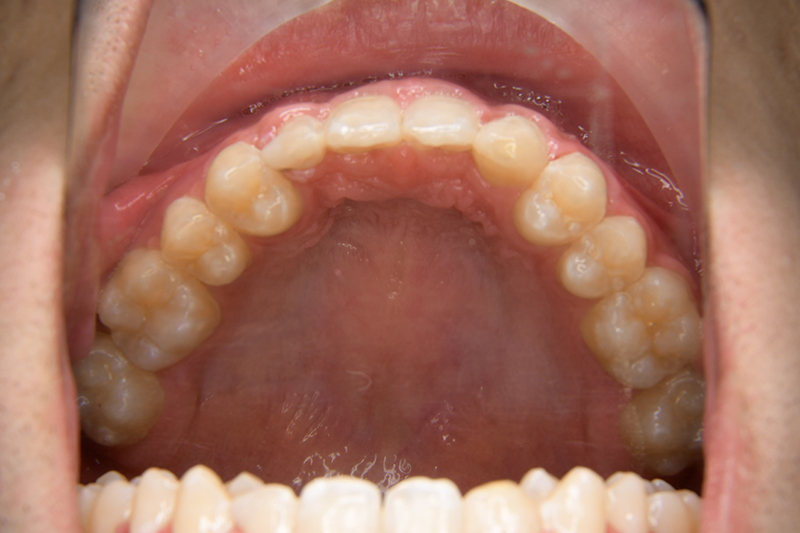

初診時

FP・IOP

主訴 すきっ歯 診断名 上顎右側犬歯先天欠如を伴うアングルⅡ級空隙歯列症例

口腔内所見 over jet 8.0mm、over bite 8.0mmで下顎歯列はスピー湾曲が強く、過蓋咬合、上突歯列、叢生歯列を呈しており、臼歯関係はⅡ級、左側7は鋏状咬合となっていた 。上顎両側2は矮小歯で上顎右側Cは晩期残存をしていた。また上顎歯列は空隙歯列を呈していた。